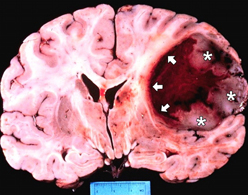

Beyin vasküler elemanlarının anevrizmalarının meydana getirdiği beyin kanamaları acil ortamlarda kar ...

Ani gelişen beyin kanamaları önemli sorunlarımızdan biridir. Genellikle kanamalar gece saatlerinde o ...

Sıcak havalarda beyin kanaması riski ve dikkat edilmesi gereken noktalar hakkında bilgi veren Prof. ...